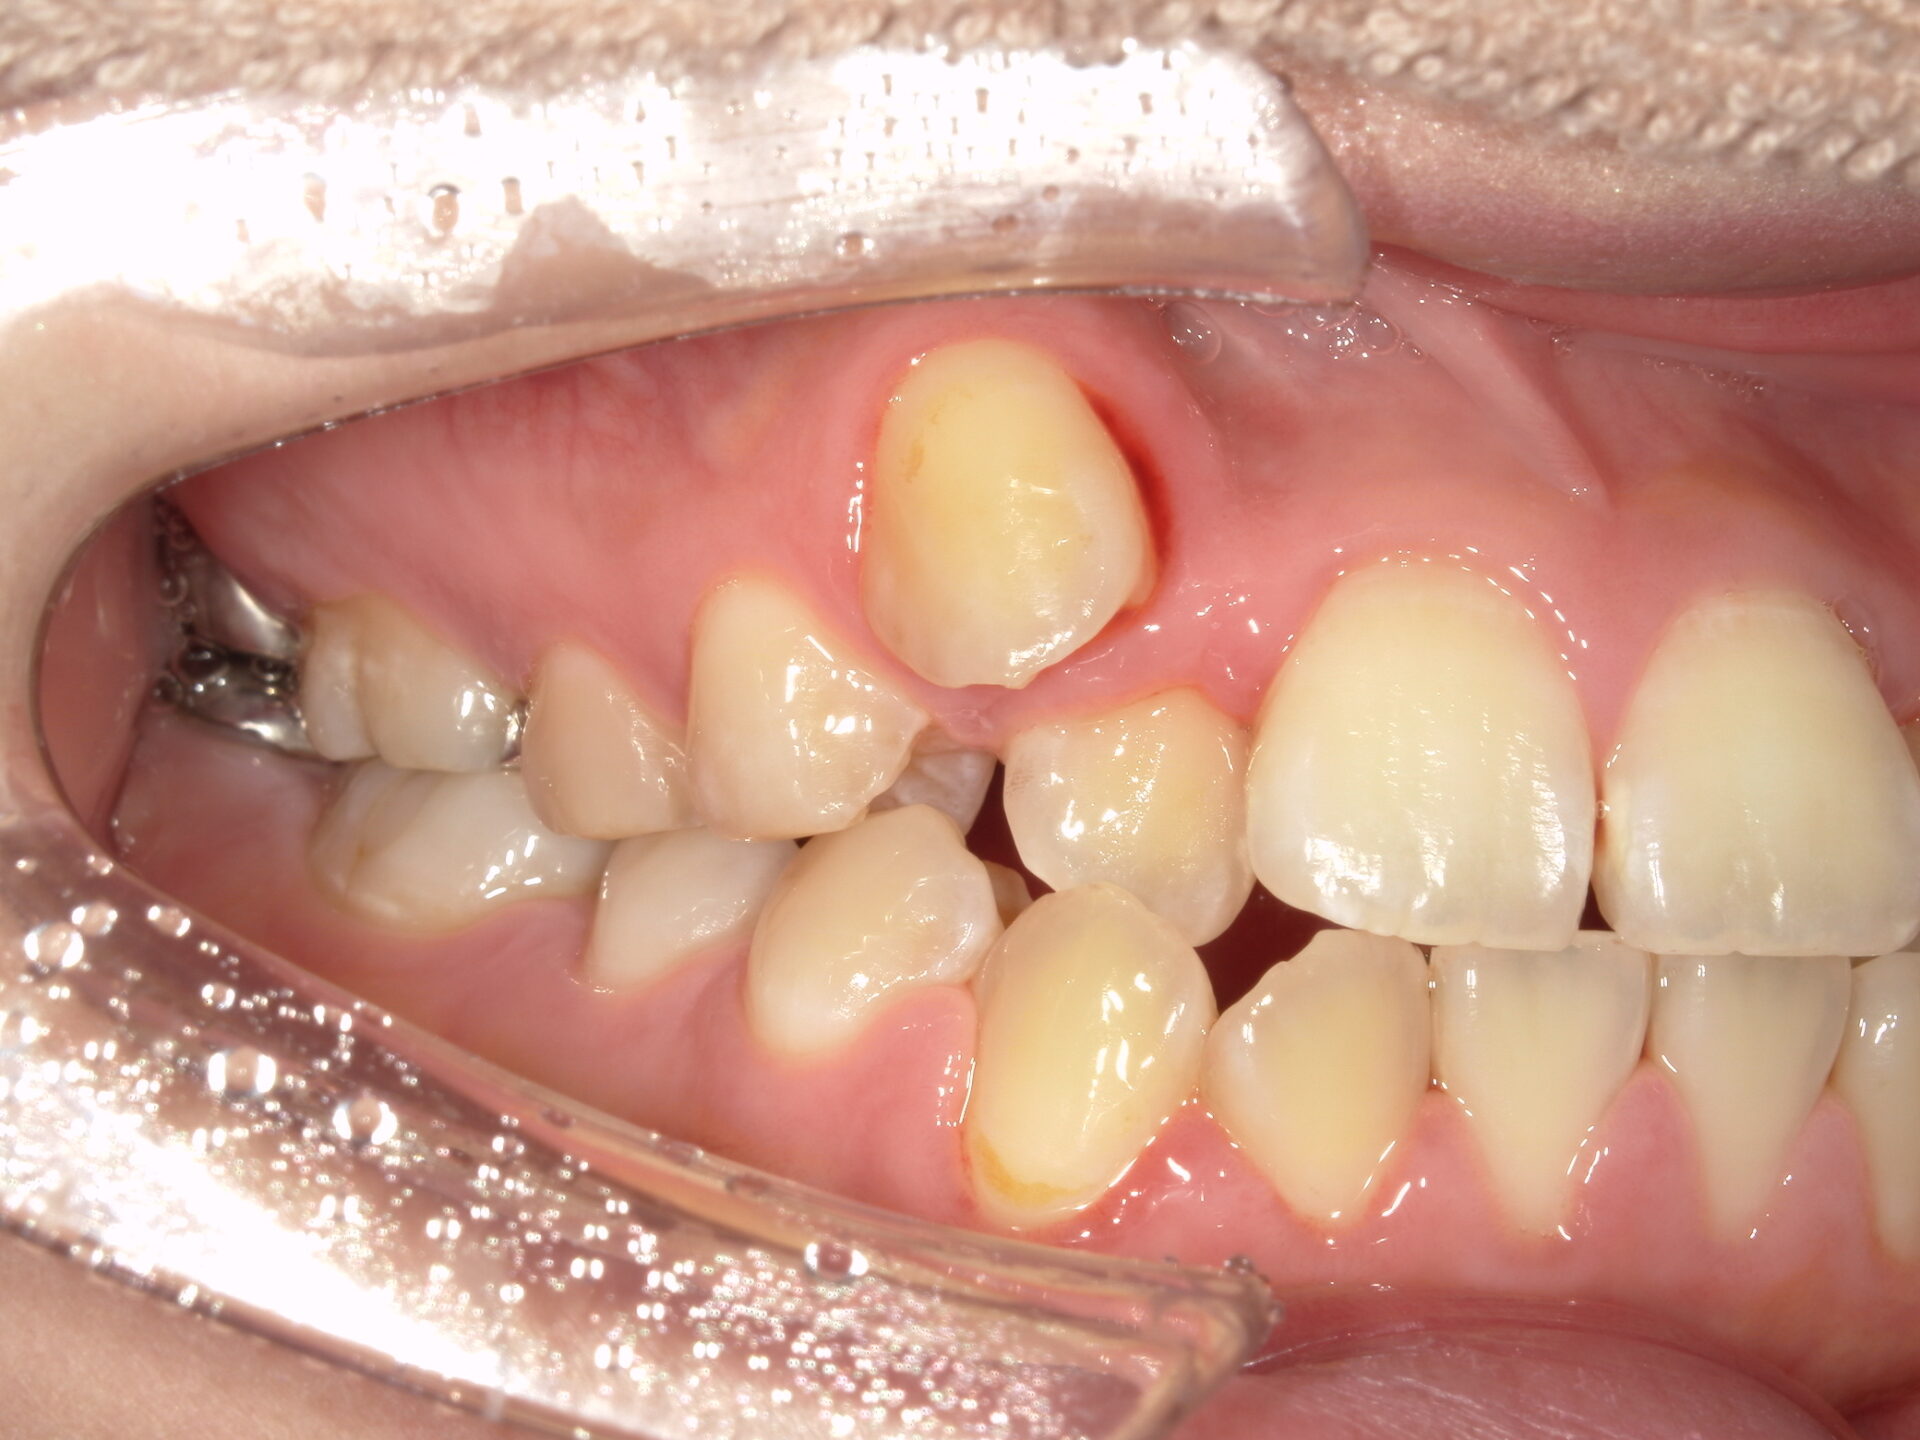

患者さんの年齢 20代 女性 症状 八重歯がコンプレックス、白い歯を入れたい 治療内容 セラミック治療 費用 費用150万(税抜) 治療期間・回数 治療期間1ヶ月・通院回数3回 メリット 治療期間・回数が少ない デメリット・リスク 術後知覚過敏が起こる事ある - セラミック治療

before

after